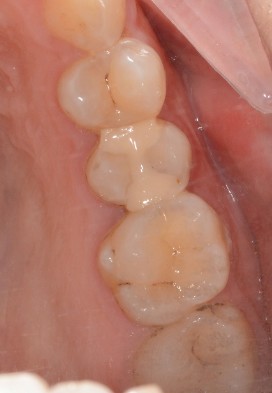

患者女,三十岁,15邻颌面大面积充填物,邻接过紧,食物嵌塞,探(+-),叩(-),冷测试正常,余无不适。很多人牙体缺损面积较大,补牙后很会出现脱落的现象,还有的让选择简单的修复模式补牙,但大量的临床研究显示,牙科树脂充填材料会产生聚合收缩(树脂材料老化),形成微渗漏,引起继发龋(顺着充填材料周围,在牙齿上出现新的腐坏、变黑)。像这种面积比较大的龋齿单纯补牙的话,不耐用。这时候就可以选择嵌体修复。嵌体牙体预备量少,能够保持牙齿外形的完整,减少对牙髓的刺激。还有就是嵌体更耐磨使用寿命较长,从而减轻了患者频繁补牙的痛苦。通过 CEREC 扫描更加精准有效的提高了我们工作效率,当天即可戴牙,正常使用。